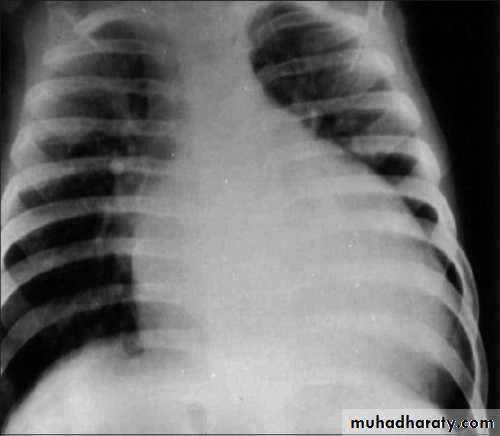

CXR: the absence of cardiomegaly on a chest x-ray usually rules out the diagnosis of heart failure.

ECG: atrial or ventricular hypertrophy, nonspecific T-wave abnormalities, and, occasionally, atrial or ventricular arrhythmias.CXR: cardiomegaly and pulmonary congestion.